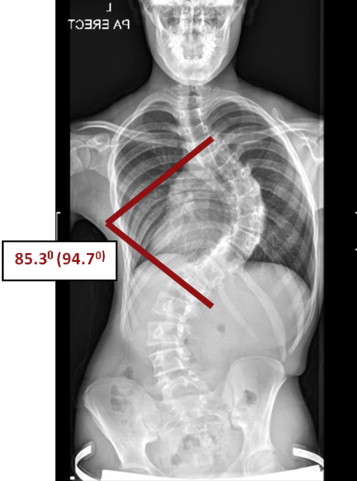

يُعد اعوجاج العمود الفقري (الجنف) من الحالات الشائعة التي تصيب الأطفال والمراهقين خلال مراحل النمو، ويمكن أن تستمر أو تظهر في مرحلة البلوغ. ومن بين العلاجات غير الجراحية الفعالة التي تُستخدم لتقويم العمود الفقري وتقليل تطور الانحناء، يبرز الحزام الطبي أو الجبيرة القطنية كأحد الحلول الأساسية، لكن يبقى السؤال: متى يجب البدء في استخدام الحزام؟ ومتى يكون غير فعال؟

انحناء يتراوح بين 25° و45° لدى المرضى الذين لا يزالون في مرحلة النمو.

الحالات التي يتجاوز فيها الانحناء 45°، حيث يصبح الحل الجراحي أكثر فاعلية.

استخدم الحزام في حالات الانحناء من 25° إلى 40°، خاصة في مراحل النمو المبكر.

تأكد من عدم وجود تحدب صدري حقيقي أو حالات متقدمة فوق 45°.